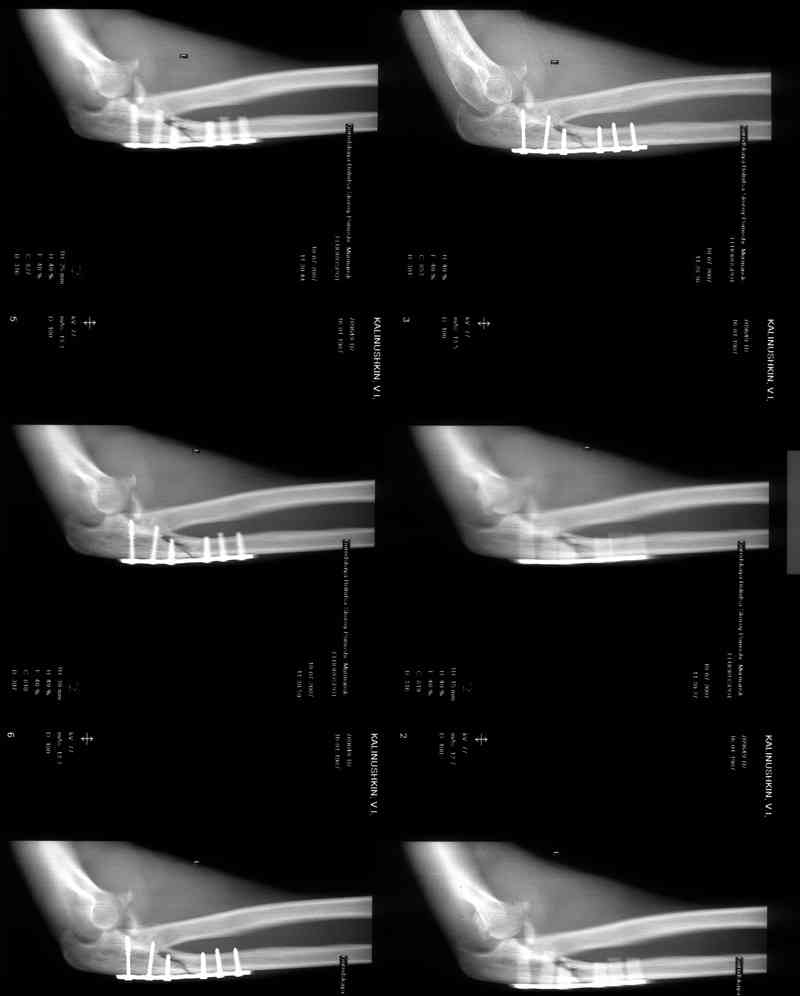

[Ortho] Несросшийся перелом локтевой кости, подвывих предплечья кзади.Перелом венечного отростка. Состояние после резекции головки лучевой. Травма 4 мес. назад.

Больной наблюдался в поликлинике,к нам попал

через 3 мес. Отмечается контрактура локтевого сустава, сгибание/разгибание 30/0/0.

МРТ у нас нет, сделаны томограммы.